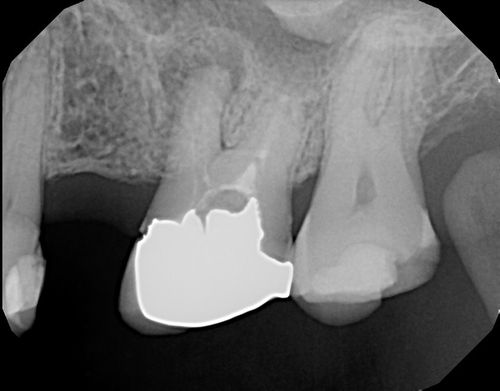

During your consultation, our expert endodontist will thoroughly examine your tooth and evaluate the need for retreatment. This will involve reviewing your dental history and taking 3-dimensional imaging of your tooth to accurately diagnose the disease.

Root Canal Filling Removal and Disinfection

Using precise techniques and advanced equipment, we will carefully remove the existing root canal filling and address any issues that may have arisen since the previous treatment. The canals will then be thoroughly disinfected and a medicated paste will be placed into the canals to help eliminate any bacteria still present. This typically will remain inside the tooth for 1-4 weeks.

Refilling the Root Canal

Once the tooth is adequately disinfected, you will return to the office for our endodontist to place the new root canal filling material within the canals. We will also place a temporary restorative material within your tooth until you are able to follow up with your general dentist.